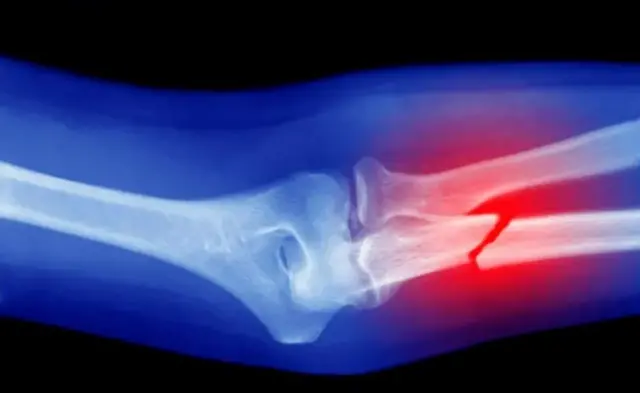

Xubnaha kale ee kobca ee kamid ah jirka bini'aadamka, waxaa kamid ah maqaarka, lafaha iyo mararka qaar kelyaha.